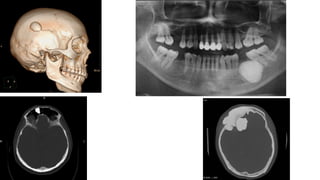

OSTEOMA

El osteoma es un tumor benigno raro de hueso, que parece tener un origen

perióstico o yuxtacortical.

Se da más a menudo en adolescentes y adultos, y tiene preferencia por el

sexo masculino.

Tipos: .- Clásico o convencional (huesos de osificación membranosa),

.- Parosteal (exostosis o hiperostosis postraumática),

.- Medular (islas óseas) y

.- Síndrome de Gardner (osteomas, poliposis colónica, tumores de

tejidos blandos. De transmisión autosómica dominante).

I. OSTEOMA

El osteoma clásico se da en el cráneo, senos paranasales y la mandíbula.

El parosteal en los huesos largos y

El medular en el tercio medio de la tibia y el fémur.

Clínica:

Los osteomas suelen ser de crecimiento lento, indoloros salvo cuando ejercen

acción mecánica sobre estructuras vecinas, pero producirán una gran masa ósea

visible y palpable. En ocasiones debuta con una sinusitis o una masa que deforma

las paredes de la órbita, o una protrusión en la mucosa bucal.

Rayos X ; La lesión es circunscrita de extraordinaria densidad, redondeada y

generalmente menor de 2 cm, aunque pueden alcanzar dimensiones enormes.